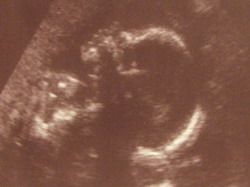

Kismanónk gyönyörű 706 gramm, 24 hetes egy naposan, pont 24 hetes egy naposat mutatott a gép is és a profilja tisztára olyan mint Áronnak. Fényképezőgépet most nemtudtunk vinni, mert nem volt benne elem, de felvette dvd-re amit meg nemtudunk megnézni mert nincs lezárva...

jaj és nagyon fiú!!! Akkora bizonyítéka van, hogy csak na!